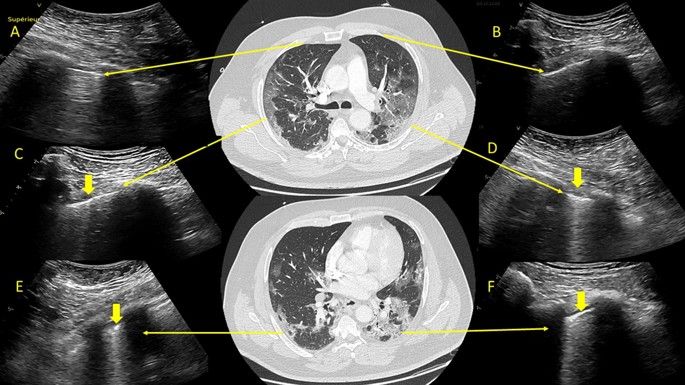

Ultrasound images distinguish vascular causes linked to three conditions.

Largest study in Europe for the evaluation of renal lesions using CEUS with a histopathological validation.